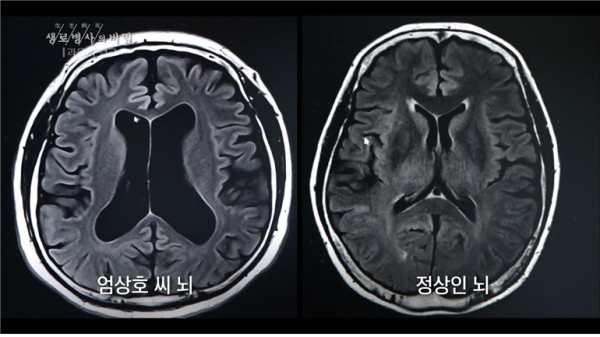

이날 ‘생로병사의 비밀’에는 알코올성 치매 전 단계와 ‘알코올 사용 장애’(알코올 의존증, 알코올 중독증) 판정을 받은 두 사람의 사례를 통해 잦은 음주와 과음이 우리 뇌에 미치는 영향과 치료법을 알아본다.

알코올성 치매가 중증으로 진행되면 치료가 어렵다고 한다. 하지만 알코올 사용 장애와 알코올성 치매 전 단계까지는 술을 끊으면 회복할 가능성이 있다고 한다. 이 때문에 알코올로 기억력이 떨어진다고 느끼면 검사와 치료가 필요하다고 예고했다.